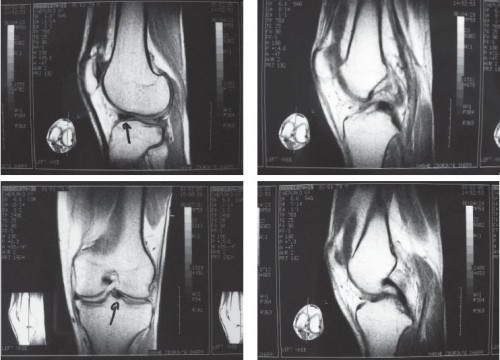

Для более детального обследования дисторсии колена назначают магнитно-резонансную томографию или компьютерную томографию с контрастированием.